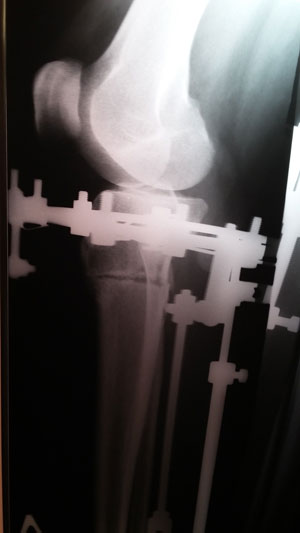

Рентген в 90 дней.

Здравствуйте, Виктория! Приезжайте на снятие аппаратов, сращение хорошее.

Напоминаю всем пациентам, что на момент снятия аппаратов обязательно делается рентген контроль (повторный снимок) в клинике.